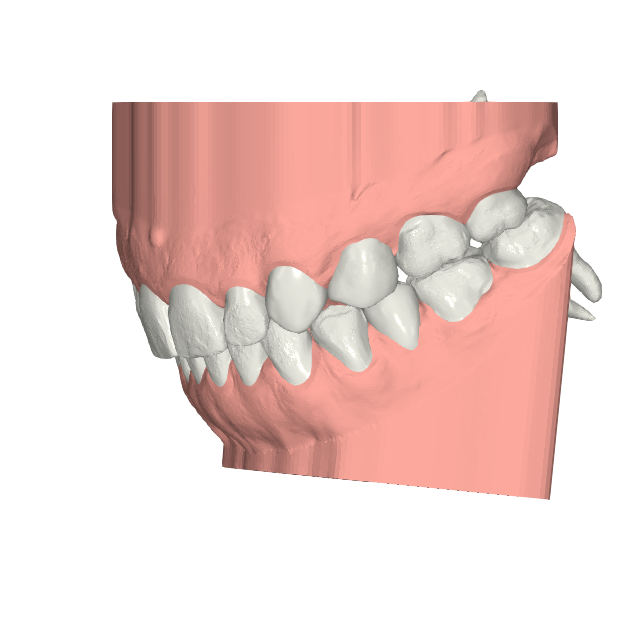

Elevantia Solutions accepted the challenge by designing a treatment plan with Ortho Root Plan Design, a tool that allows orthodontic planning based on the exact position and movement of roots during treatment. This is essential for complex cases because it reduces risks, prevents root damage, and ensures maximum predictability

Ortho Movements

The proposed design corrected midline discrepancies, improved occlusion, and established the foundation for future restorative work. Thanks to this advanced approach, the treatment was safer, more conservative, and highly predictable, providing security for the doctor and confidence for the patient